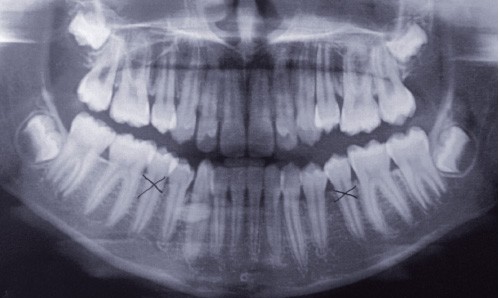

Une jeune patiente de treize ans est adressée par son orthodontiste à la suite de la découverte fortuite, à l’orthopantomogramme (OPT), d’une lésion radio-opaque (fig. 1).

La patiente ne présente pas d’antécédent médico-chirurgical. Le palper bidigital met en évidence une masse centimétrique, dure, mobile, au niveau du plancher buccal droit. L’expression de la glande submandibulaire droite ne fait pas apparaître de salive à l’ostium du canal de Wharton. Un examen tomodensitométrique (TDM) est réalisé (fig. 2).

Il met en évidence une opacité se projetant au niveau du tiers moyen du plancher buccal.

Exceptionnellement, c’est l’OPT qui permet le diagnostic positif, mettant en évidence une image radio-opaque se projetant au niveau…